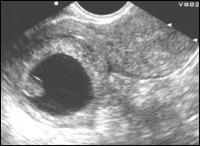

| Рисунок 1

| Эхографические признаки внематочной беременности Эктопически расположенное плодное яйцо с живым эмбрионом (в 5-10%) (развивающаяся беременность)